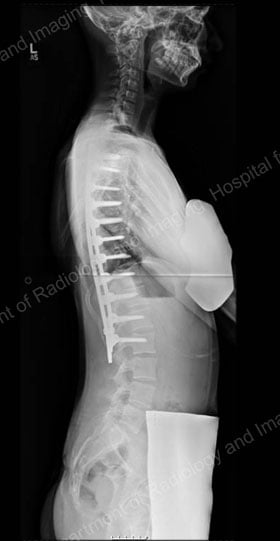

During the healing process, which takes 6 to 12 months in an adolescent, the spine is held in alignment by hooks, screws or other instrumentation. Once the fusion is complete, the implants no longer serve a function but are left in place to avoid the need for additional surgery [Figures 7 & 8].

Figures 7 (left) & 8 (right): Postsurgical posterior and lateral X-rays of the same patient shown in Figures 4 & 5: results achieved with a posterior approach.